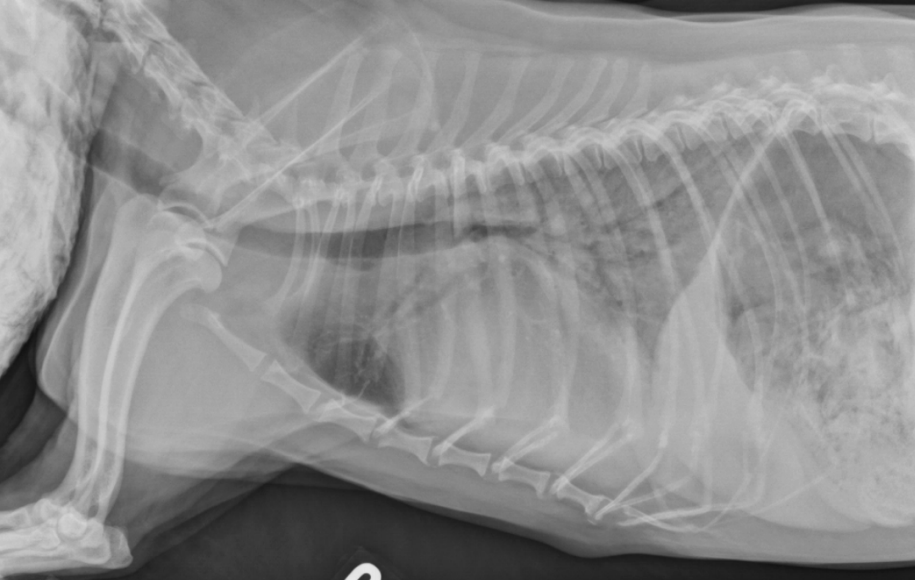

● 7 yo castrated male Golden

Retriever

● Lethargy for last 24h

fat along cranioventral aspect of thorax, maybe fluid too at heart apex.

pericardial effusion: very round heart margin tells you its fluid and not just cardiomegaly.

mild bronchial pattern